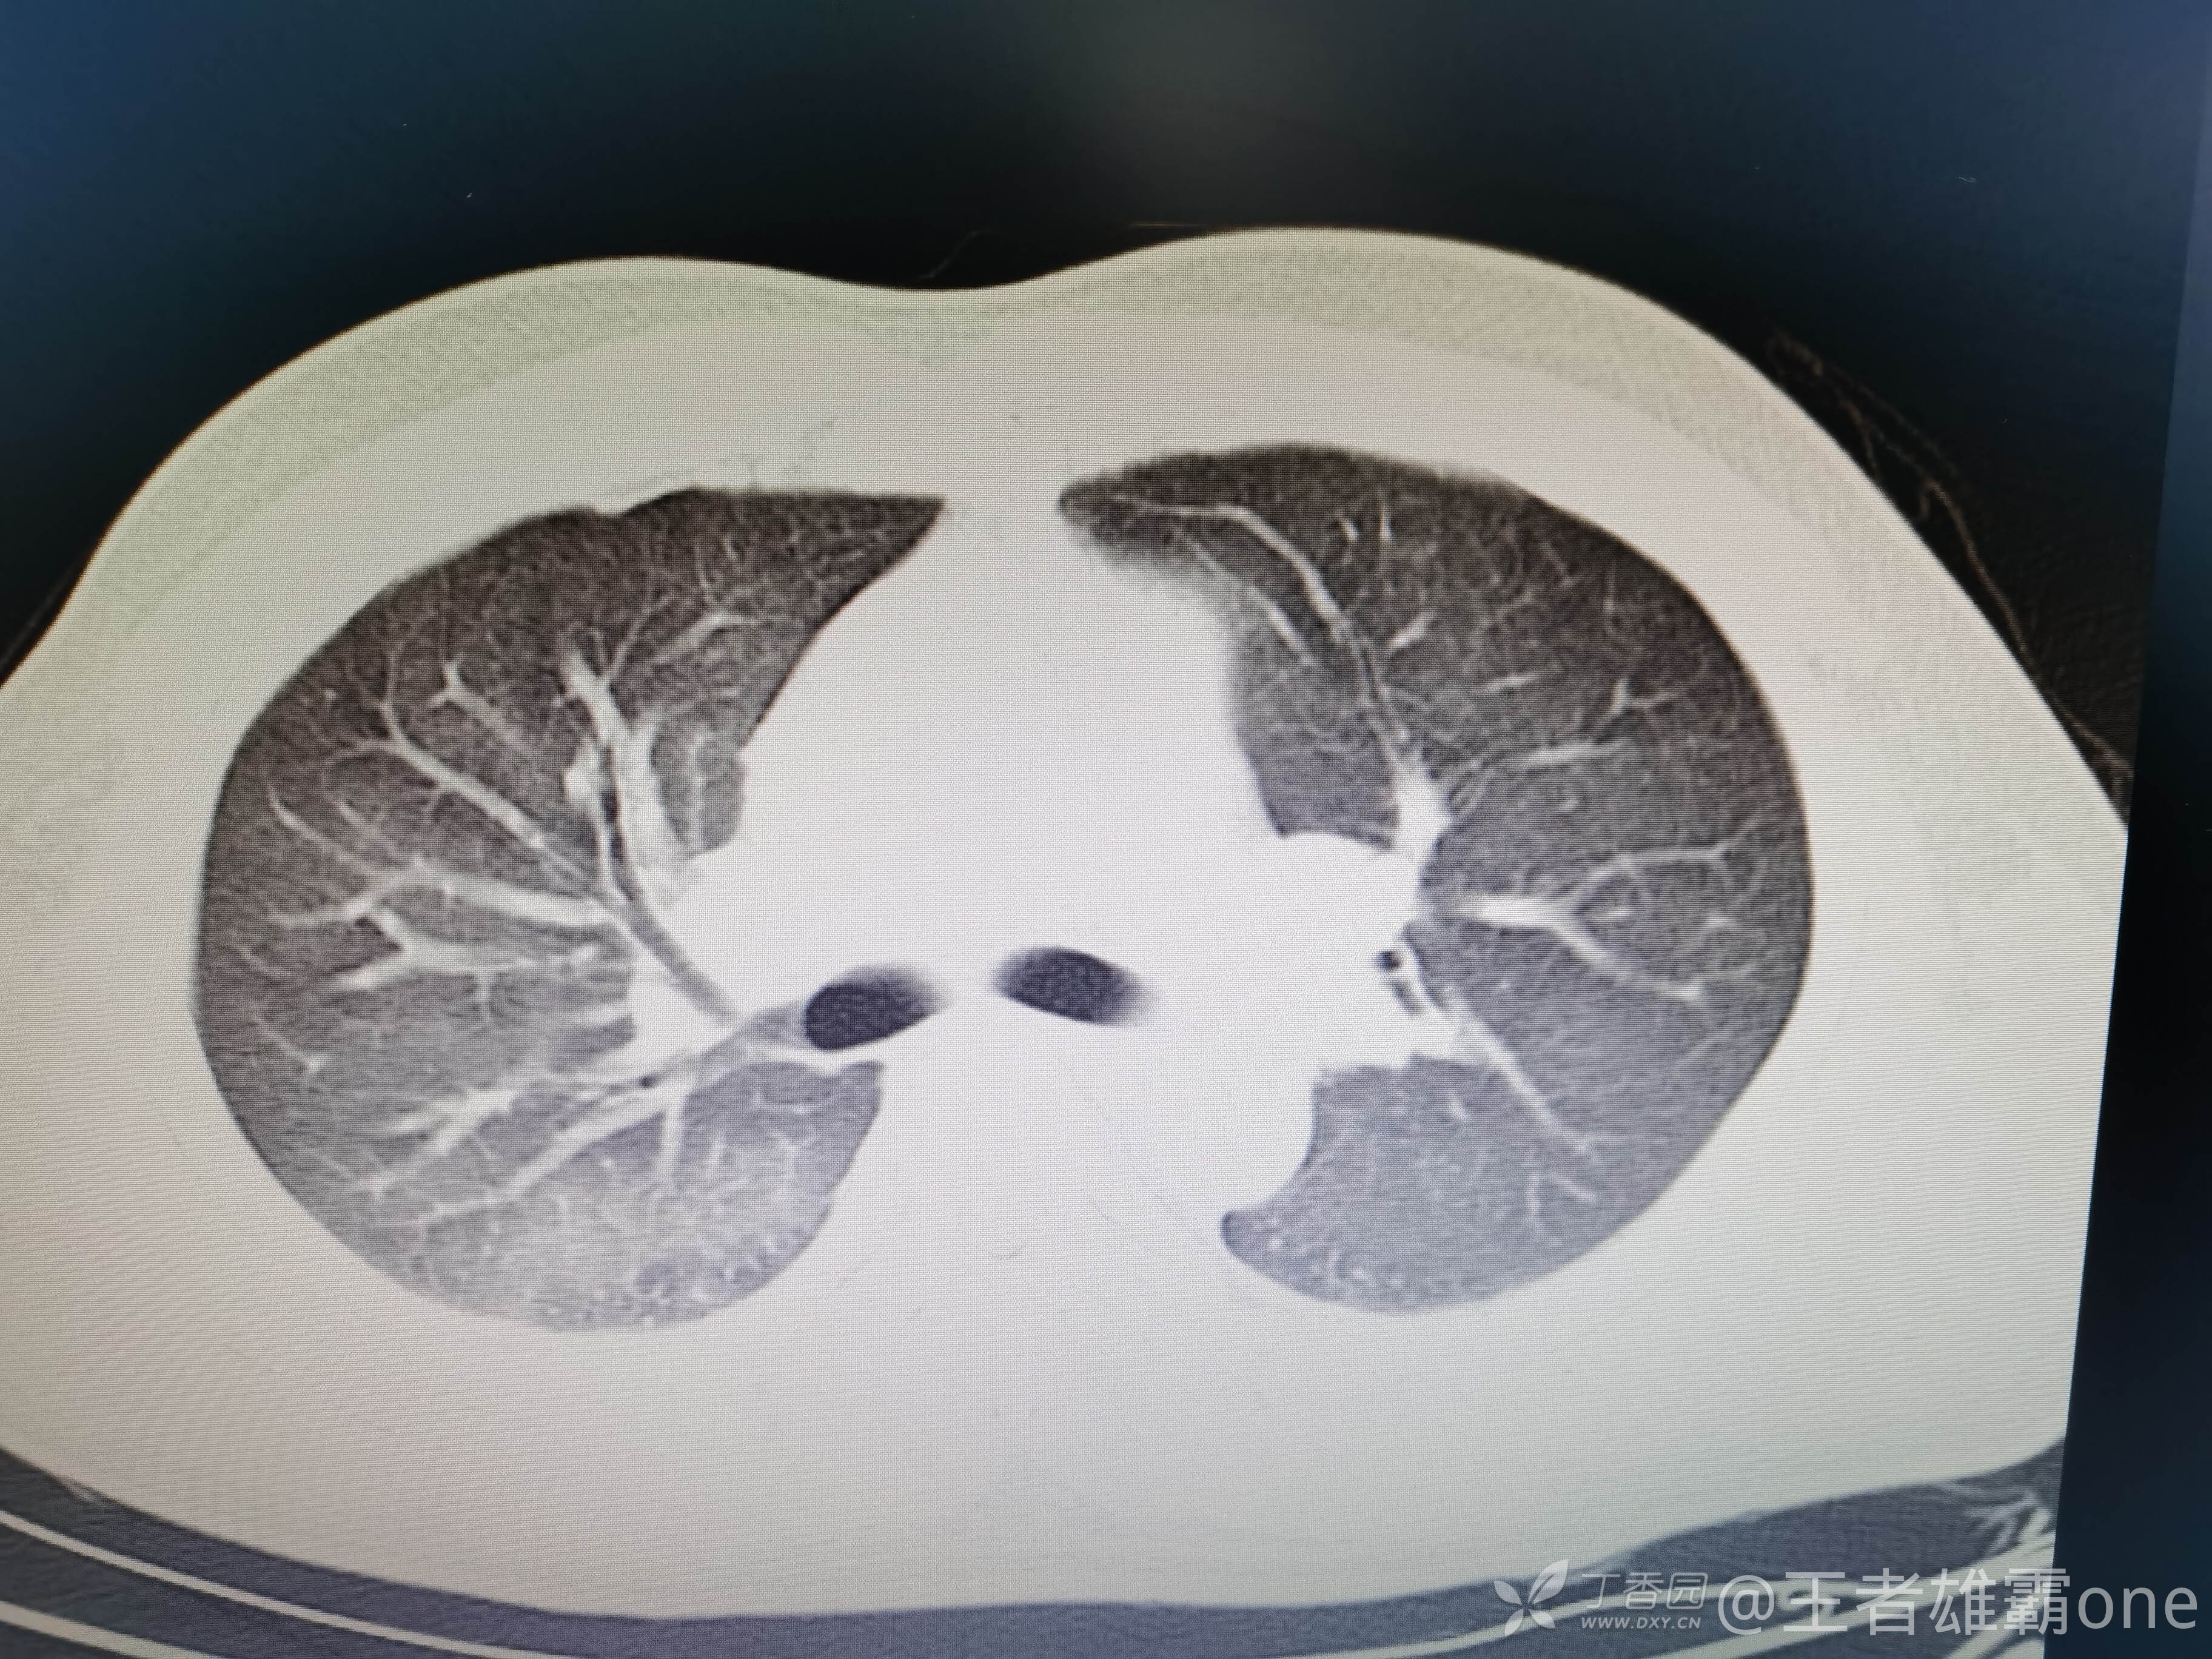

西门开心 推荐男,33岁,否认既往有心脏基础疾病,6-1受伤后急诊行右胫腓骨骨折固定术(术前胸部CT无明显异常,见后面视频前半部分),术后逐渐出现刺激性咳嗽、胸闷,无精神症状,无皮疹,无胸痛,无咯血等。6-6完善胸部CT、脑钠肽前体、心超等辅查,其中脑钠肽前体、心超无明显异常。复查的胸部CT见视频后半部分:

附几张CT图片: